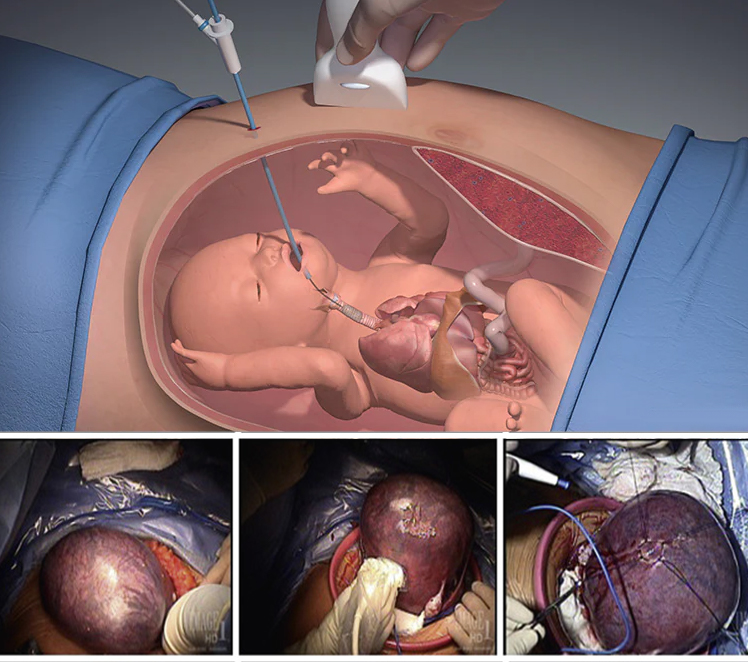

تشمل هذه الخدمة التدخلات الجراحية التي تجُرى أثناء الحمل لعلاج الحالات المرضية التي يمكن أن تؤث ر على الجنين.

- الجراحة بالمنظار : تستخدم أدوات جراحية دقيقة وكاميرا لفحص وعلاج الجنين دون الحاجة إلى فتح كبير.

- التدخلات الطبية : مثل نقل الدم داخل الرحم في حالات فقر الدم الشديد عند الجنين.